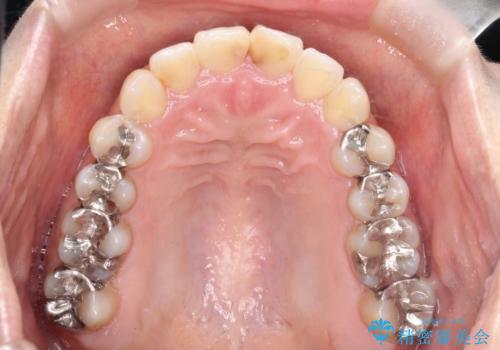

前歯のガタつきをマウスピース矯正で改善! 驚きの効果を体験しよう

- 前歯のガタツキが気になると来院されました。

マウスピース矯正治療を選択しました。

奥歯の噛み合わせは綺麗に噛んでいたため、前歯の叢生(でこぼこ)に集中して治療するように計画しました。

奥歯の噛み合わせは整っていたため、前歯の並びを美しく修正することに専念できました。